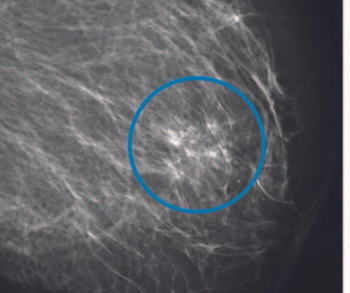

In a large study of nearly 100,000 women, researchers found that the combination of digital breast tomosynthesis (DBT) and synthesized mammography had more than triple the detection rate for invasive breast cancer in extremely dense breasts in comparison to digital mammography alone.

Women who had enhancing lesions associated with low-energy findings were more than twice as likely to have malignancy in comparison to those who had enhancing lesions without low-energy findings.